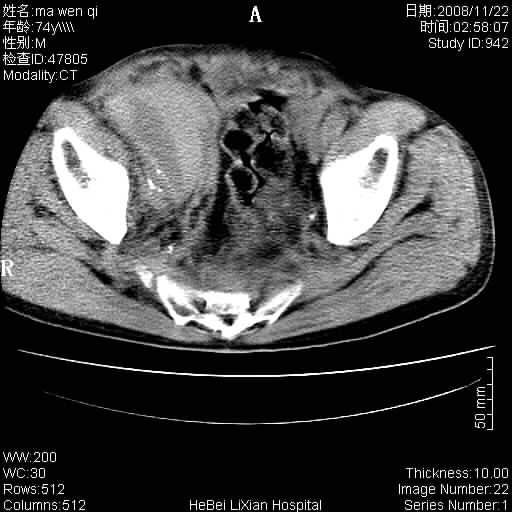

患者男 74岁.突然昏迷,休克6小时.血压70/30,头颅ct未见异常,既往体健.

补充病史,保留导尿10小时,尿袋内只有少许尿液,患者于住院后15小时后去世.

腹主动脉、双侧髂动脉夹层动脉瘤破裂出血进入腹腔。

考虑双侧髂a瘤,伴破裂出血

腹主动脉、双侧髂动脉夹层或动脉瘤破裂出血进入腹腔

1)考虑双侧髂动脉瘤并右侧动脉瘤破裂出血,右侧腹膜后及腹腔积血。2)双侧腹股沟疝。

支持(1)双侧髂动脉瘤并右侧动脉瘤破裂出血,右侧腹膜后及腹腔积血。(2)双侧腹股沟疝。

1)考虑,腹主动脉、双侧髂动脉夹层动脉瘤破裂伴右侧腹膜后及腹腔积血。2)双侧腹股沟疝。

1)考虑胸、腹主动脉、双侧髂动脉瘤并右侧动脉瘤破裂出血,右侧腹膜后及腹腔积血。2)双侧腹股沟疝。